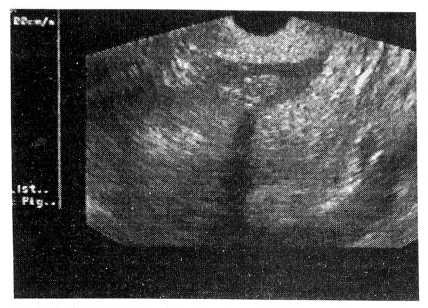

УЗИ матки показало сравнительно быструю инволюцию матки при ушивании ее викрилом, более гомогенную эхоструктуру швов, меньшую толщину стенки в области рубца. При использовании кетгута во время анэхогенного контрастирования у женщин выявлялись дефекты миометрия в виде неровности внутреннего контура полости матки и “ниши” (рис. 1).

Рис. 1 Трансвагинальное сканирование с анэхогенным контрастированием. Дефект в виде ниши в области послеоперационного шва на матке.